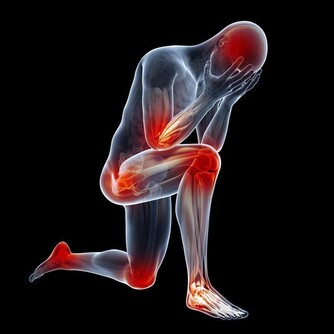

2.增加肌肉:你可能覺得要有肌肉都要重訓。但走路其實最能幫助增加肌肉,不僅能讓腿部、腹部、臀部的肌肉更結實,甚至還能訓練到腹肌跟腰部。

3. 鍛鍊心臟又降低血壓:研究也發現,每日走路可以降低心血管疾病和高血壓的風險,對心臟也更健康。